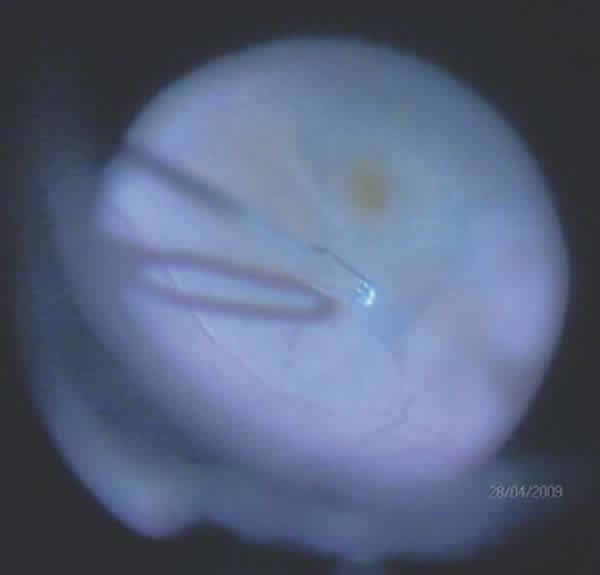

Corticoids

Corticoids are a group of hormones which, in addition to being produced naturally in the supra-renal cortex, can also be synthesized. Corticoids are frequently used in clinics. Triamcinolone acetonide (TA)is a synthetic corticoid insoluble in water having the empirical formula C24H31FO6 and a molecular weight of 434 daltons. Fluometholone acetate (FMA) is a fluorinated glucocorticoid having the formula C24H31FO5 and a molecular weight of 418 daltons. Both corticoids can be utilized in surgery for their anti-inflammatory effect as well as for staining the vitreous by means of depositing crystals on it. TA is marketed under the trade name of Triesence (Alcon Labs, Forth Worth, TX, 40 mg/mL); Kenalog (Bristol-Myers-Squibb, Peapack, NJ, 40 mg/mL); Trivaris (Allergan, Irvine, CA, 80 mg/mL); and in Spain as Trigon Depot (Squibb, 40 mg/mL).

Kimura et al first utilized TA for peeling ILM as a result of the crystals sedimentation over the ILM which facilitated its identification and elimination with good clinical results and without adverse effects 3 months later (fig. 11). Comparing these results with those of ICG staining in macular hole cases, a similar rate of closures without adverse effects have been described.